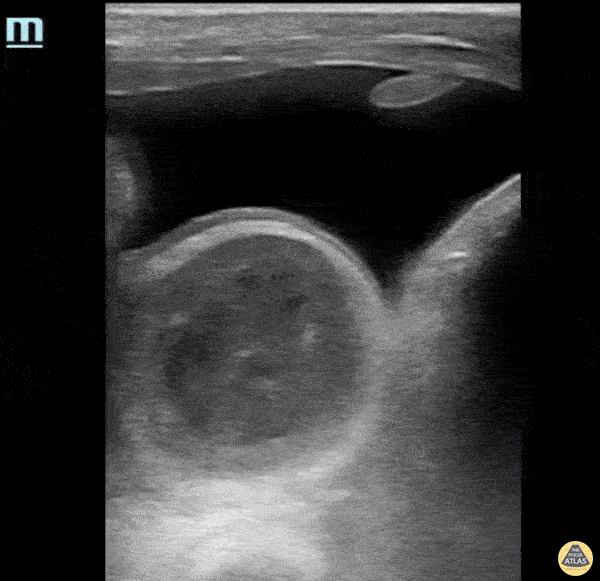

This patient presented with acute onset, severe groin pain. On physical exam, a large inguinal hernia was appreciated, and the scrotum was enlarged, erythematous, and exquisitely tender to palpation. POCUS exam was performed and there were multiple bowel loops with active peristalsis and a large anechoic fluid collection. CT imaging confirmed this fluid to be a herniated portion of the bladder, which likely provided a good acoustic window for clear visualisation of the bowel loops. Catherine Barrington MD, MSc, PGY1 Emergency Medicine, CMU; Andrew Namespetra MB BCh BAO, MSc, PGY3 Emergency Medicine, CMU